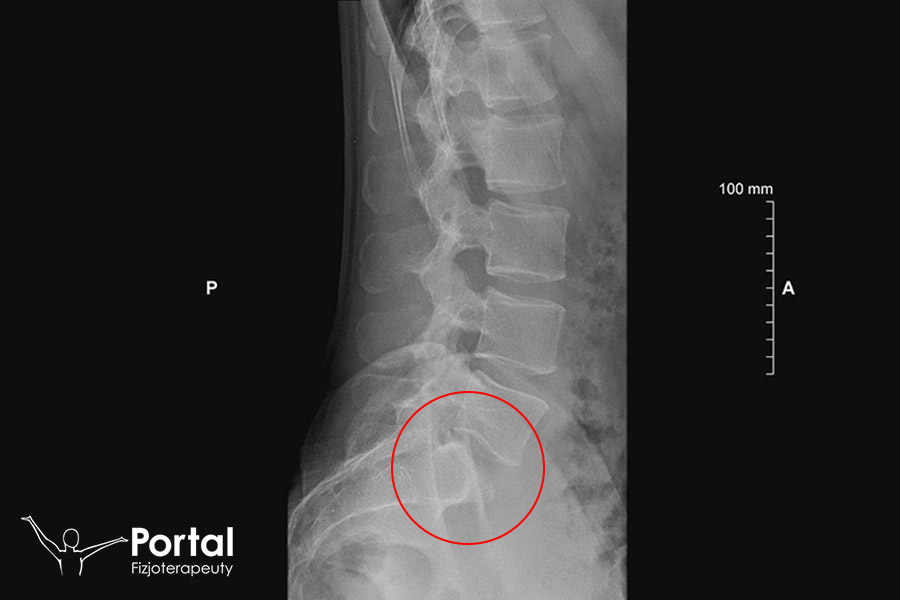

Rozpoznanie kręgozmyku jest proste. Zazwyczaj wiele można ustalić już na podstawie szczegółowego wywiadu oraz testów funkcjonalnych. Jednak pełne rozpoznanie ustala się na podstawie badania RTG wykonanego w projekcji bocznej, przednio-tylnej i skośnej. Ze względu na stopień przemieszczenia kręgów wyróżniamy 4 stopnie kręgozmyku:

- I – przemieszczenie o 1/4 szerokości trzonu;

- II – przemieszczenie o połowę trzonu;

- III – przemieszczenie o 3/4 trzonu;

- IV – całkowite przemieszczenie trzonów względem siebie.

Na tej podstawie ustala się optymalne leczenie. Zazwyczaj stopień I i II leczy się zachowawczo z dobrym rezultatem, zaś stopień III i IV jest wskazaniem do rozważenia operacji.